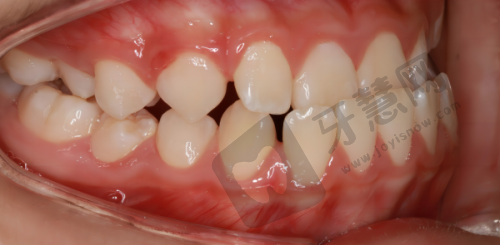

全好口腔热门的牙齿矫正项目

特别多人希望拥有整齐牙齿,不仅为美观,更为口腔健康,全好口腔的牙齿矫正项目是热门选择。它提供多种牙齿矫正方法,满足不同患者需求。传统金属托槽矫正价格相对亲民,几千元起,通过在牙齿上粘贴金属托槽,利用钢丝力量移动牙齿达到矫正目的,技术成熟,矫正成效稳定,适合牙齿排列不齐较重度的患者。隐形矫正近年来受欢迎,采用透明矫正器,几乎看不出来,不影响美观,佩戴舒适,患者可自行摘戴,方便清洁口腔,价格相对较高,一万元起。全好口腔医生根据患者牙齿状况和需求推荐合适矫正方法,矫正过程中定期复查,根据牙齿移动情况调整方案,还为患者提供口腔护理建议,帮助度过矫正期。特别多患者在全好口腔矫正后,牙齿变整齐,自信心增强。